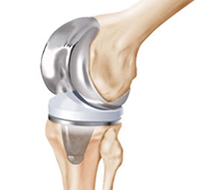

There are two main types of surgery, depending on the condition of the knee: total knee replacement and partial (half) knee replacement. A total knee replacement involves removing the damaged articular cartilage surfaces at the end of the thigh bone and the top of the tibia (the knee joint), and replacing them with a prosthetic (man-made) joint.